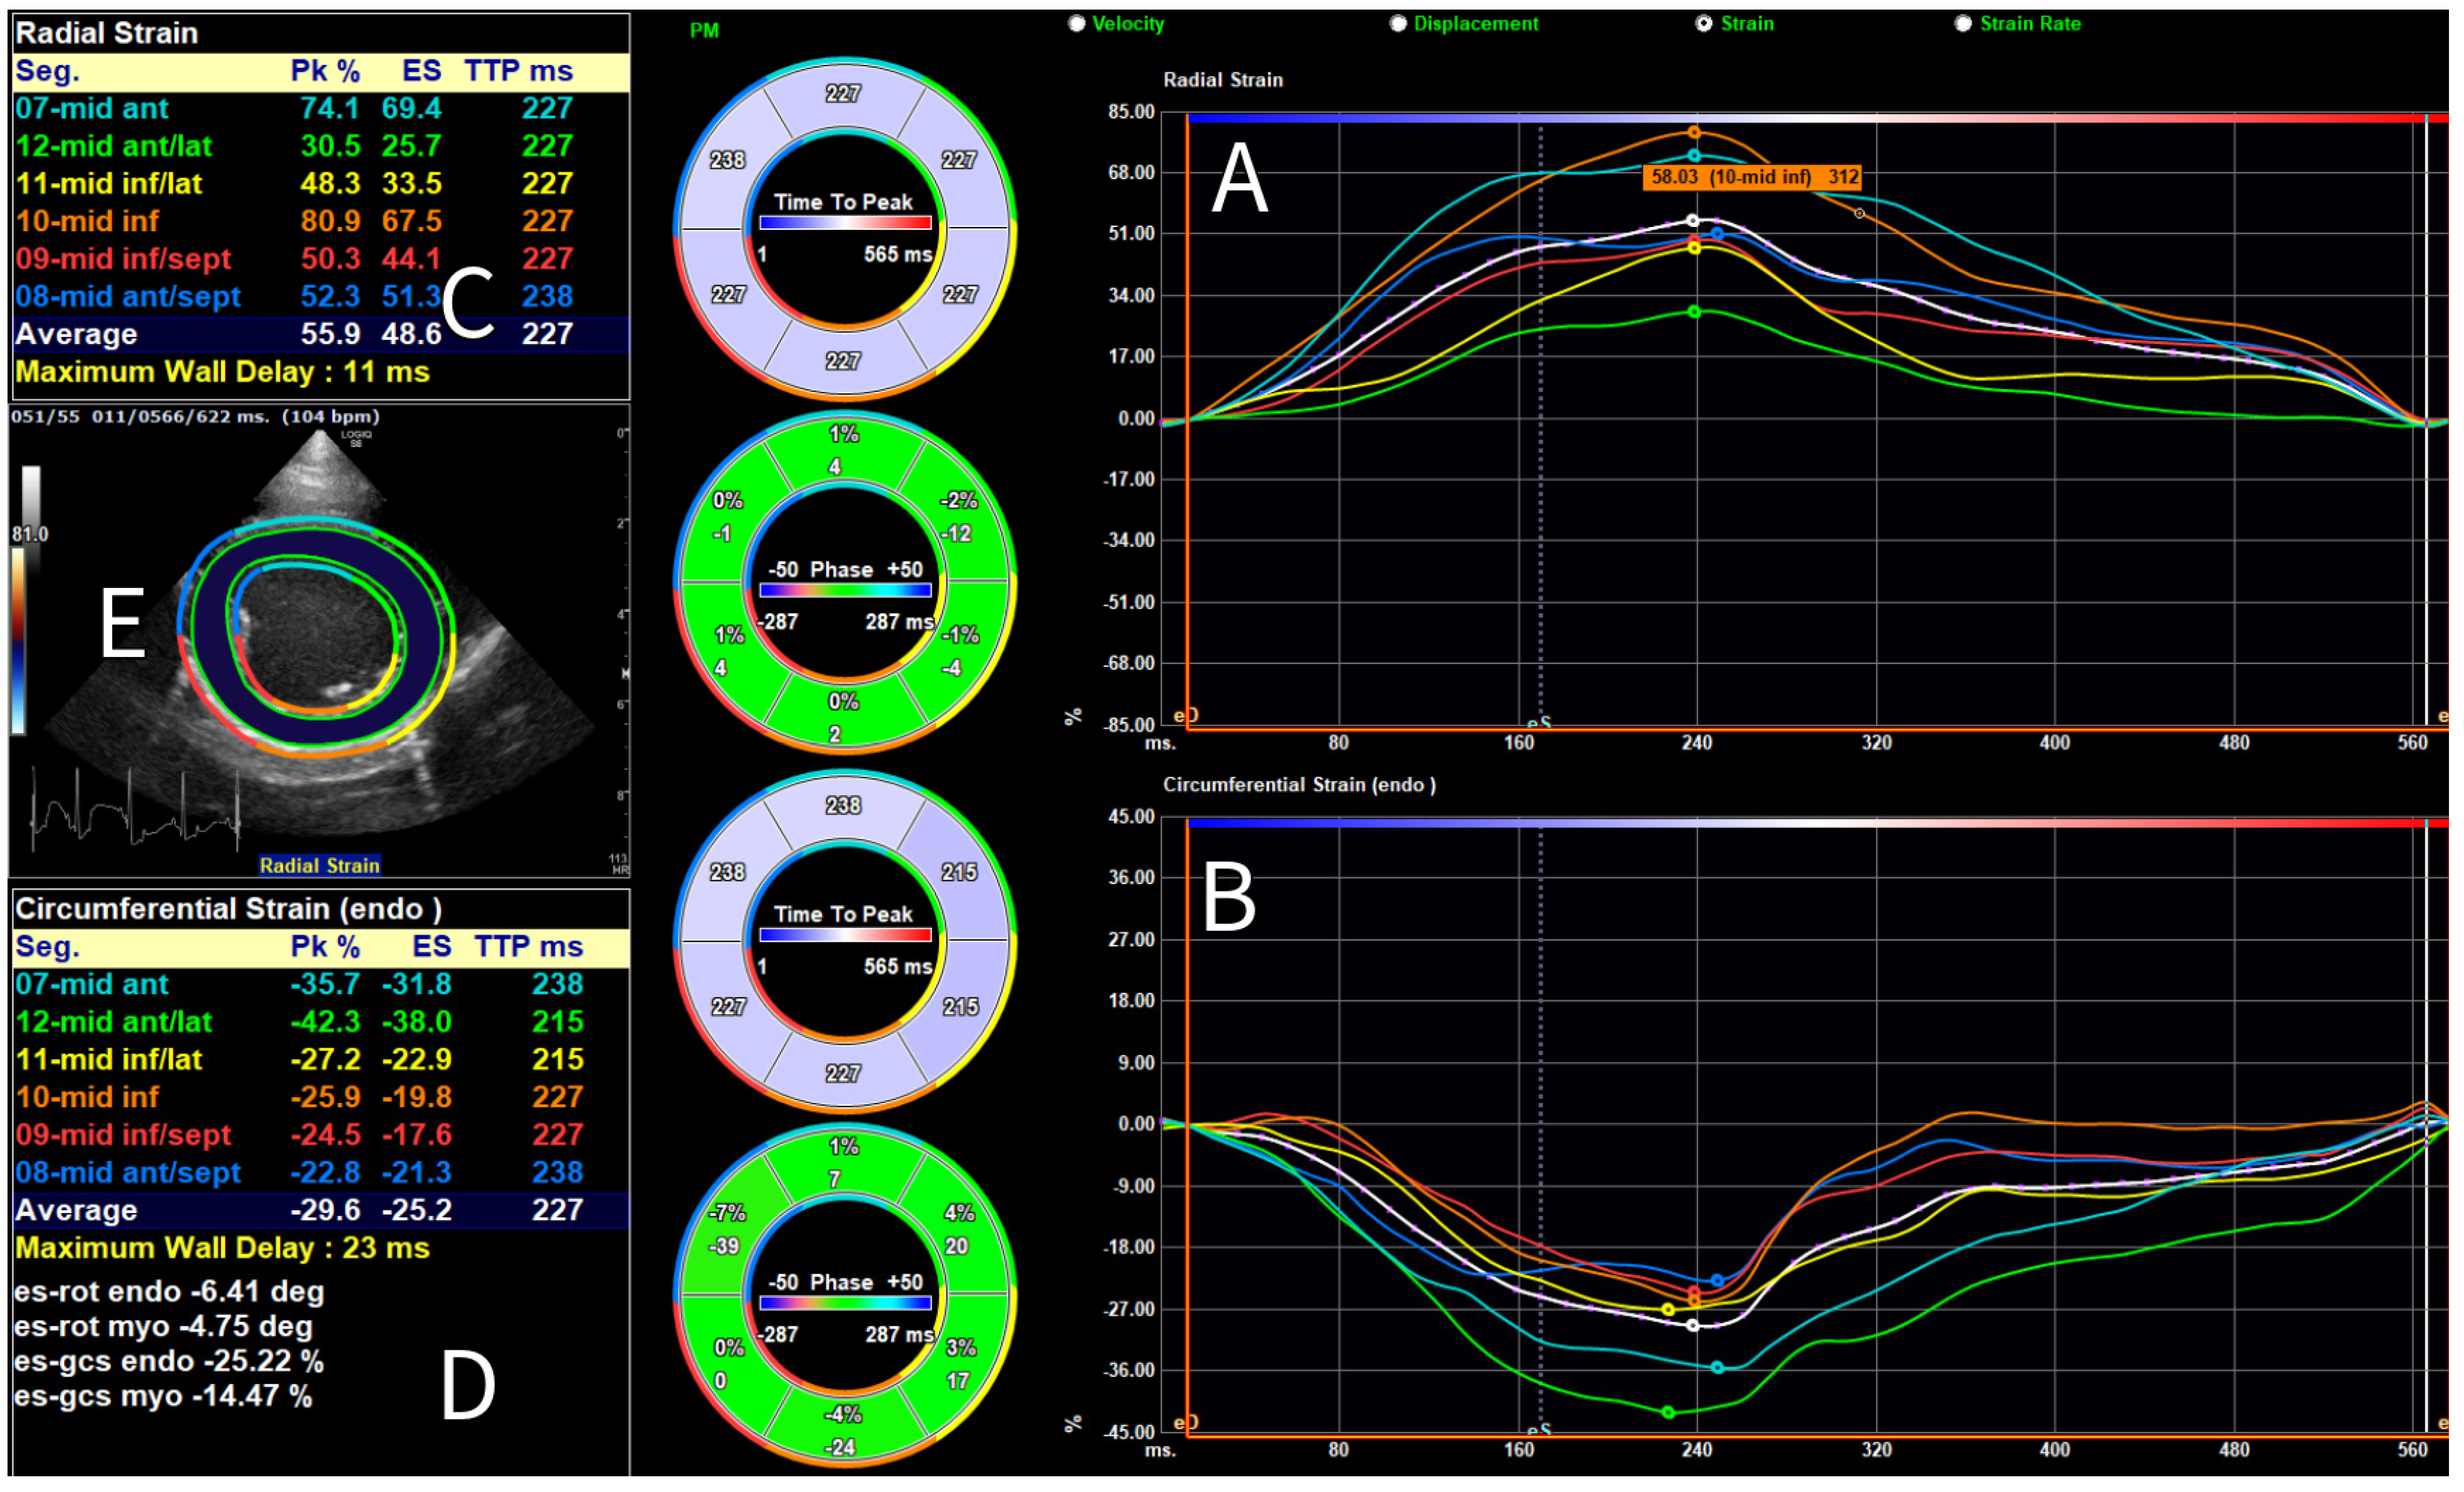

3.2. Results of Strain Analysis